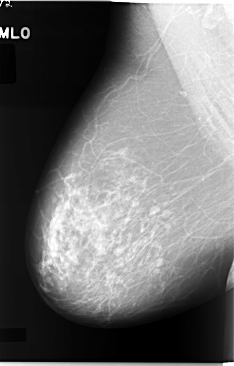

ics_version 1.0 filename C-0044-1 DATE_OF_STUDY 17 2 1993 PATIENT_AGE 64 FILM FILM_TYPE REGULAR DENSITY 2 DATE_DIGITIZED 5 11 1997 DIGITIZER LUMISYS LASER SEQUENCE LEFT_CC LINES 5872 PIXELS_PER_LINE 3624 BITS_PER_PIXEL 12 RESOLUTION 50 OVERLAY LEFT_MLO LINES 5816 PIXELS_PER_LINE 3648 BITS_PER_PIXEL 12 RESOLUTION 50 OVERLAY RIGHT_CC LINES 5864 PIXELS_PER_LINE 3688 BITS_PER_PIXEL 12 RESOLUTION 50 NON_OVERLAY RIGHT_MLO LINES 5848 PIXELS_PER_LINE 3744 BITS_PER_PIXEL 12 RESOLUTION 50 NON_OVERLAY |